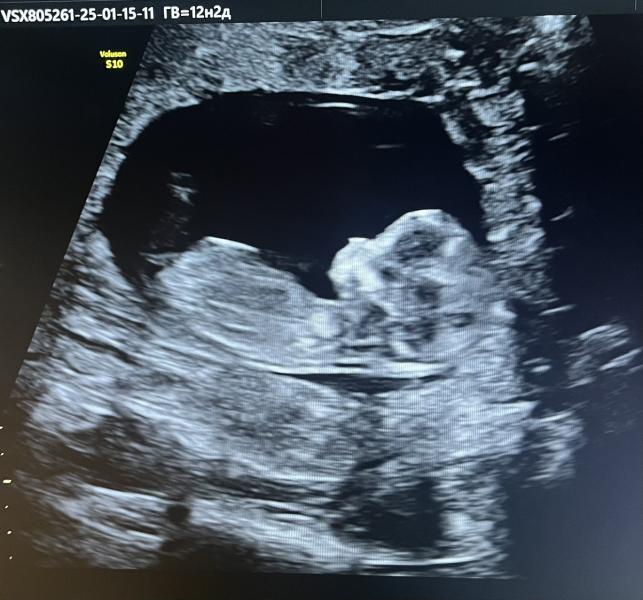

Сегодня был первый скрининг. Малыш уже больше похож на человека😍

Болтает там ножками ручками и смешно подпрыгивает пузиком кверху🤣

По узи врачи сказали, что все в норме, осталось теперь дождаться результаты крови🤞🏻

Кстати срок стал на 2 дня больше, чем по КД. Сказали теперь считать по скринингу.